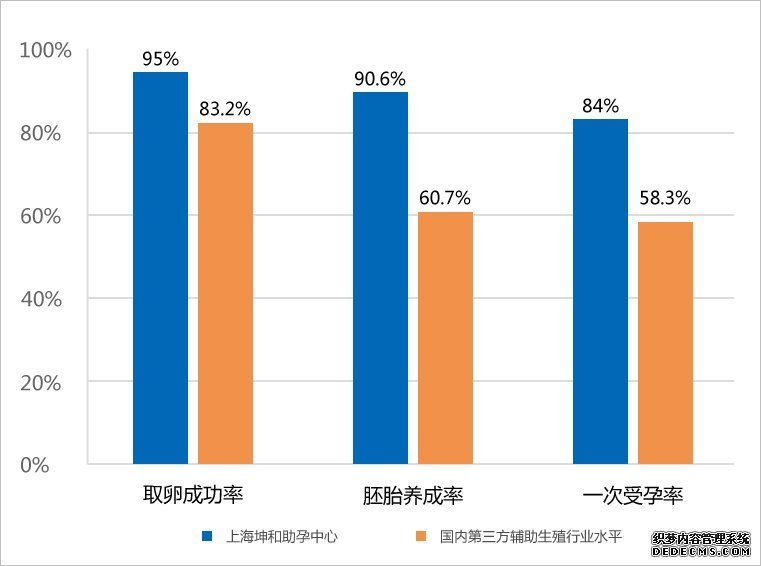

首先,我们从整个试管婴儿全套流程中来看笙笙试管中心成功率,据李博士介绍:成功率最重要的三个考察关键点分别是促排取卵、胚胎养成及胚胎移植。

笙笙试管中心成功率介绍

据中国疾病预防控制中心(CDC)报告,笙笙试管中心在35岁以上女性患者的试管婴儿治疗中,以95%的促排取卵成功率,90.6%的胚胎养成率,平均84%的 一次受孕率获得好评。

除此以外,笙笙试管中心在国内抽样的卵巢存储功能下降的患者群体中,也以52%的卵巢早衰患者比例,38.2%的治愈成功率位列国内第三方辅助生殖领域第一名。